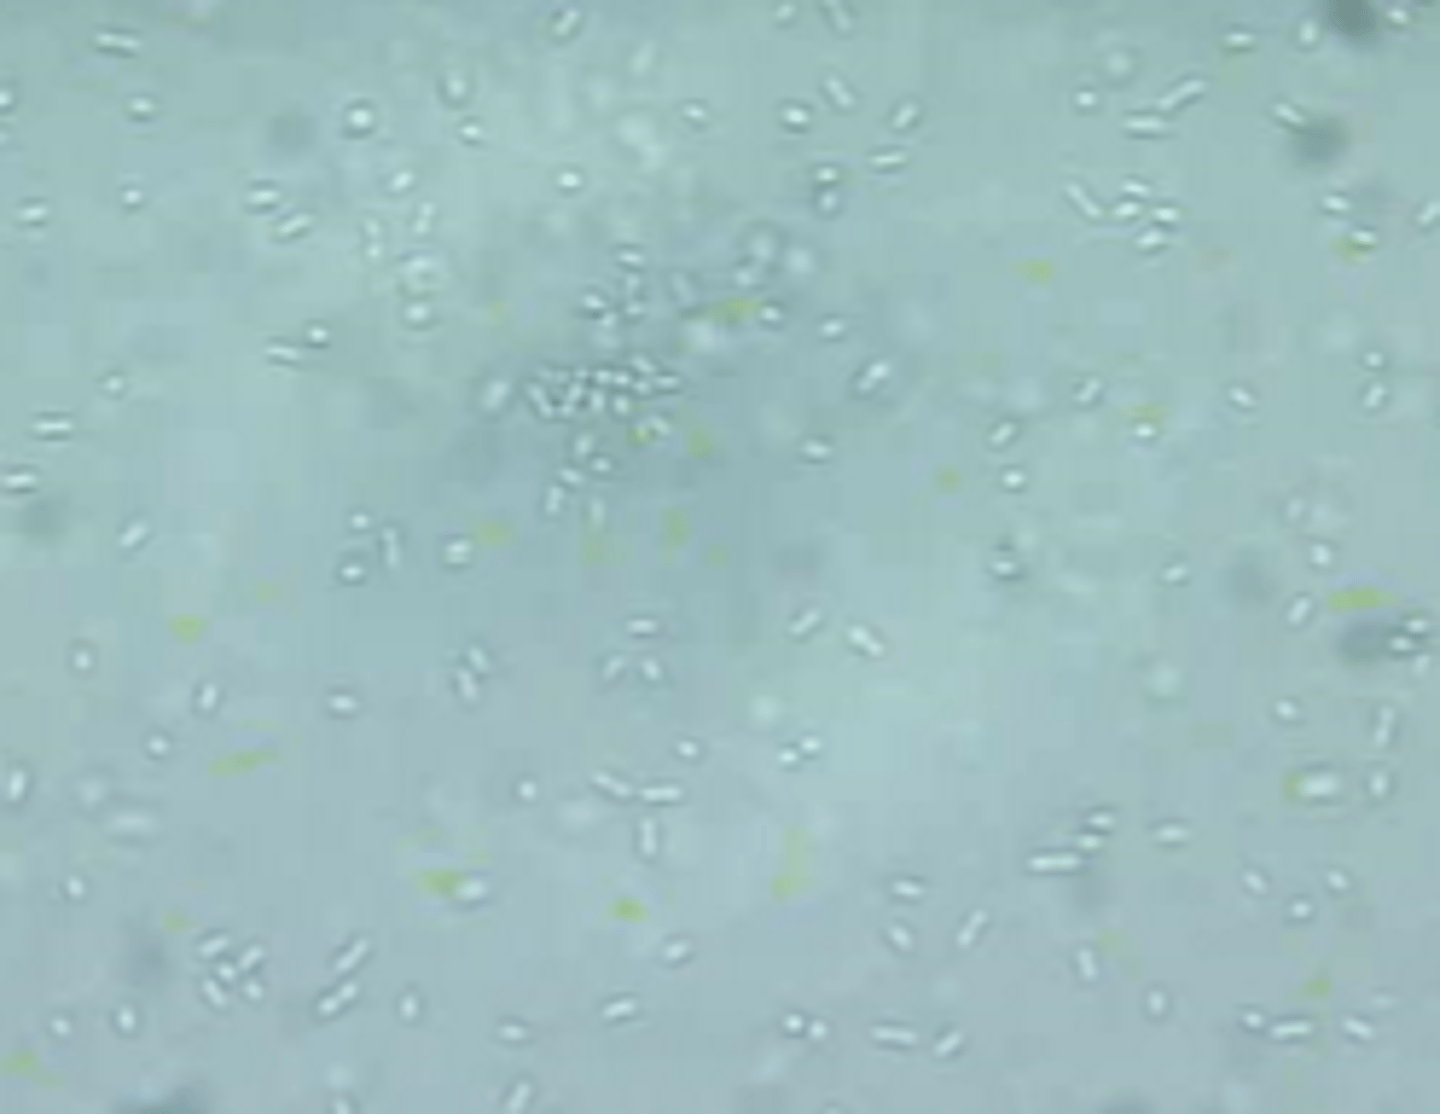

bacteria (wiggles, cocci or rods)

urine